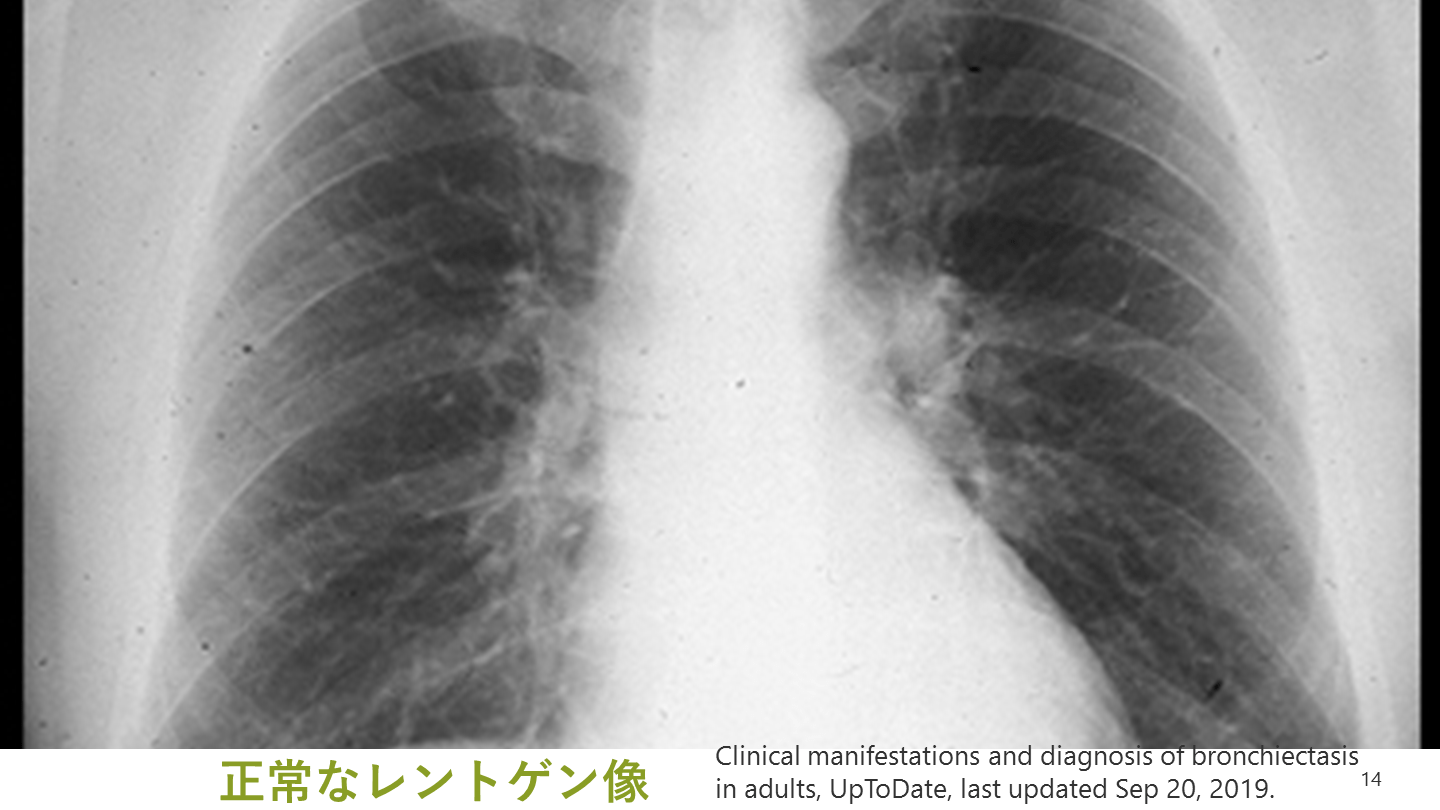

レントゲンで注意すべき所見 多くの気管支拡張症症例では異常像を示す 異常所見(単独で確定診断はできない) 線状無気肺 気管支の肥厚・拡張 不整な末梢陰影(粘液栓を示唆) Clinical manifestations and diagnosis of bronchiectasis in adults, UpToDate, last updated Sep 20, 2019.

#14.

14 正常なレントゲン像 Clinical manifestations and diagnosis of bronchiectasis in adults, UpToDate, last updated Sep 20, 2019.